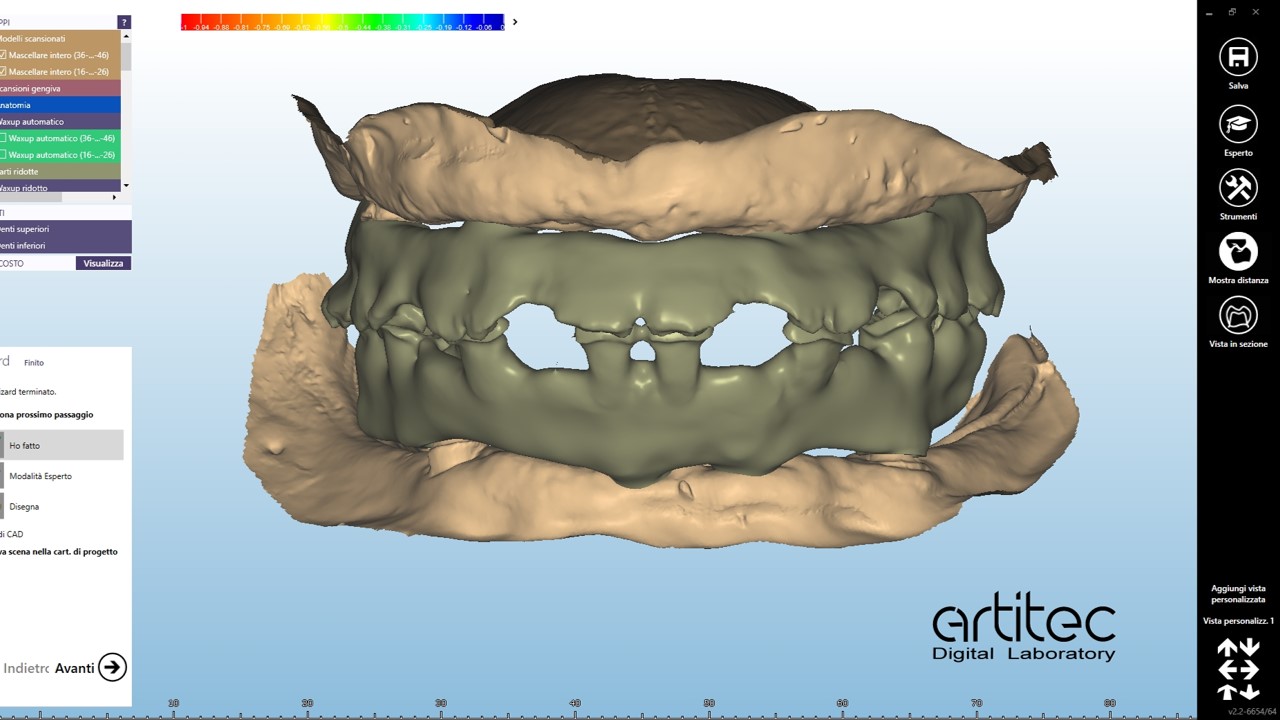

foto 08 scansione in occlusione protesi ribasate

La fase protesica inizia con la ribasatura delle protesi provvisorie per rilevare la corretta anatomia della cresta. Quindi si procede a scansionare con scansione intraorale le impronte ottenute fuori dal cavo orale, poi le protesi provvisorie ribasate ricollocate nel cavo orale e la loro occlusione. Infine, si scansionano le creste edentule dopo aver posizionato gli scan body per tecnica digitale per rilevare la posizione degli impianti. Per la pianificazione sono scattate delle fotografie intraorali ed extraorali per la definizione dei limiti perimetrali del volto al fine di poter eseguire la programmazione del caso tramite il software di previsualizzazione. Le scansioni così ottenute sono poi inviate al laboratorio per la realizzazione di un prototipo delle protesi in prova.